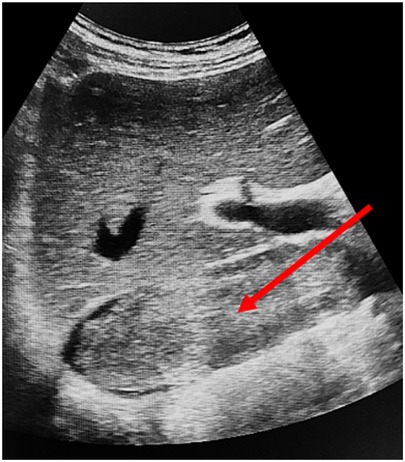

AbstractBackground:Tumor thrombus extending into the inferior vena cava (IVC) in patients with renal cell carcinoma (RCC), particularly at Mayo levels III and IV, presents a major surgical challenge. Although systemic treatments are evolving, surgery remains the mainstay of management. The role of cardiopulmonary bypass (CPB) in this setting is not clearly defined.Methods:We retrospectively analyzed 20 patients with RCC and Mayo level III–IV IVC tumor thrombus who underwent radical nephrectomy with IVC thrombectomy at our center between 2017 and 2024. Preoperative workup included MRI, contrast-enhanced CT, and transthoracic/transesophageal echocardiography. CPB was used selectively in five patients with tumor extension into and adherence to the right atrium. Postoperative complications were classified using the Clavien–Dindo system. Survival was assessed with Kaplan–Meier analysis and Cox regression.Results:Median age was 61 years (IQR 51–72), and 70% were male. Level IV thrombus was present in 60% of patients, and 40% had distant metastases. Median operative time was 370 minutes and median blood loss was 2,500 mL. Postoperative complications occurred in 20% of patients, with one in-hospital death (5%). Median hospital stay was 11 days. The 1-, 3-, and 5-year overall survival rates were 66.7%, 41.6%, and 34.6%, respectively. Distant metastases were associated with lower survival (HR 2.48; p = 0.005), while immuno-targeted therapy improved outcomes (HR 0.69; p = 0.035).Conclusion:Radical nephrectomy with IVC thrombectomy in patients with advanced tumor thrombus can be performed safely with good long-term outcomes in selected cases. Careful preoperative imaging, intraoperative echocardiography, and the selective use of CPB are key to minimizing risks. These findings support a tailored surgical approach based on thrombus level and clinical condition. Further prospective studies are needed to refine surgical indications and clarify the role of systemic therapy.